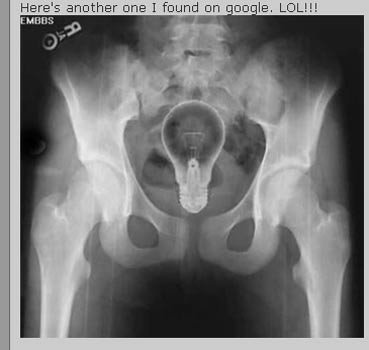

Trong trường hợp này thì sáng kiến nhét bóng đèn vào người lại là một tối kiến